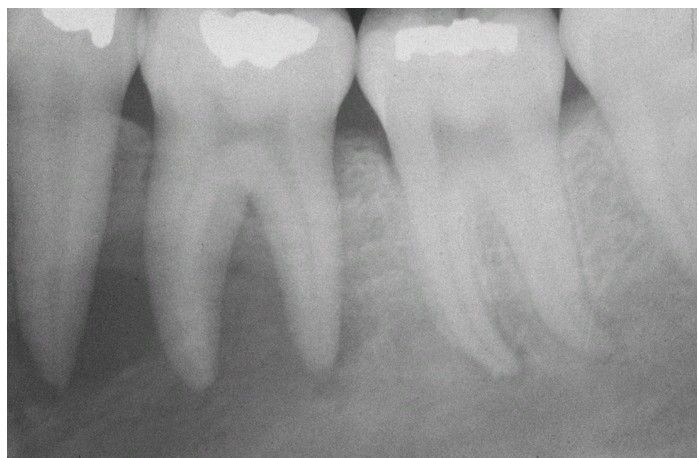

Massive Osteolysis.

Periapical radiograph showing an ill-defined radiolucency associated with vital mandibular teeth. Note the loss of lamina dura.